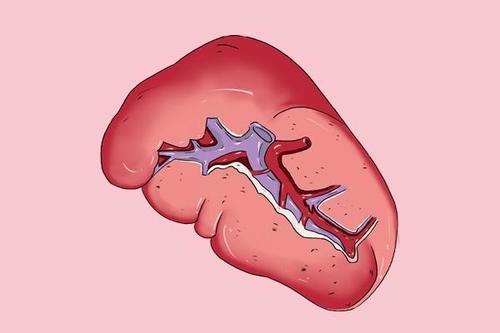

有一条沟,是神经,血管出入之处,称脾门,上缘前部有2-3个切迹,称脾切迹

上缘 superior border2.脾切迹 splenic notch3.